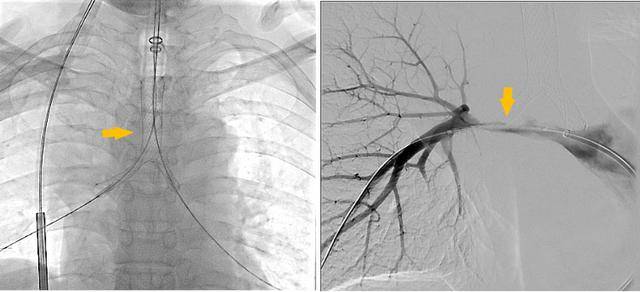

手术过程

潍坊市第二人民医院完成首例气管支架、肺动脉覆膜支架同期植入术